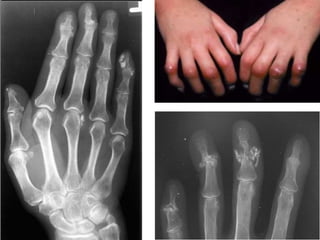

Skeletal manifestations of

scleroderma

Location:

• The hands are the most common location.

Pathology:

Radiology:

Bone changes:

• Acro-osteolysis (resorption of terminal phalanges).

• Joint space narrowing.

• Erosions.

Soft tissue changes:

• Subcutaneous & peri-articular calcification.

• Atrophy specially at the tips of finger.

• Flexion deformities.

Acro-osteolysis

terminal phalanx resorption